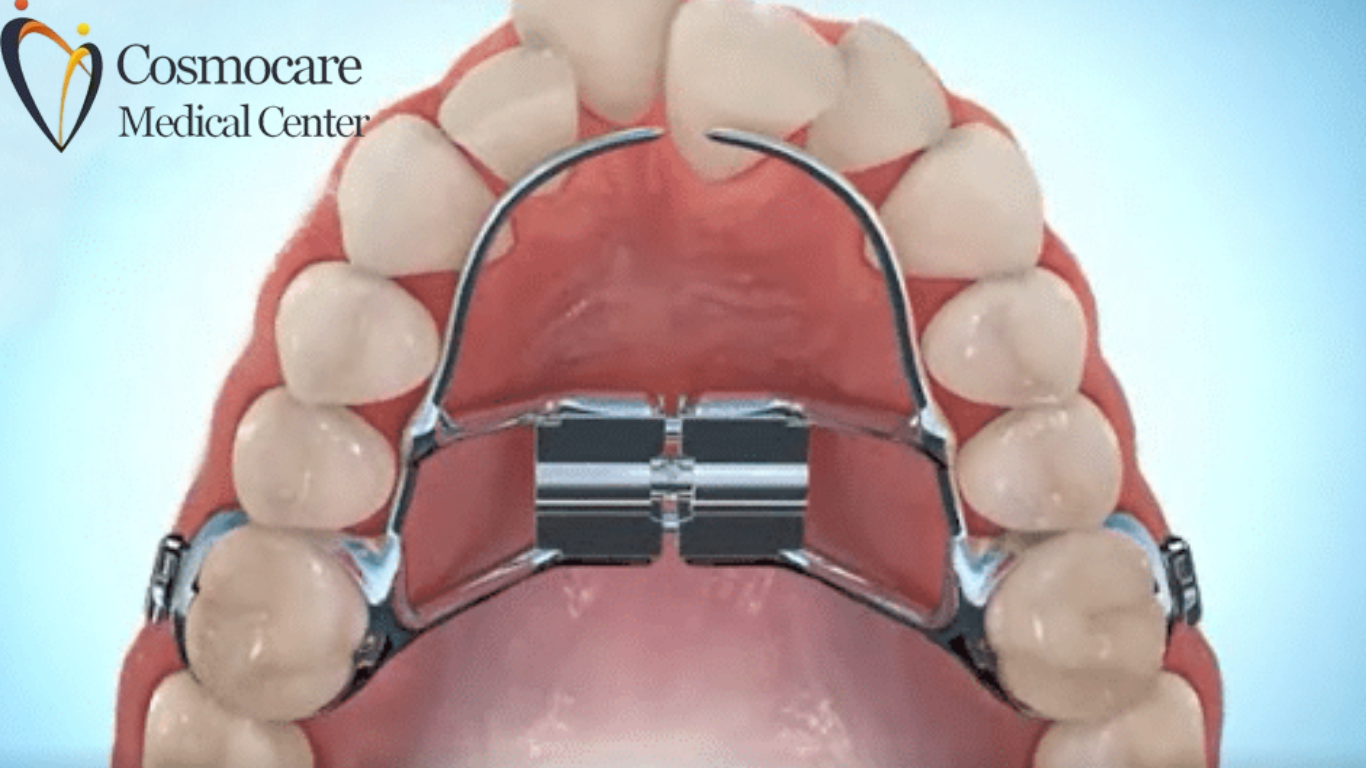

What Is a Palatal Expander?

A Palatal Expander is a custom-fitted device used to widen the upper jaw (maxilla) during growth years. This creates more room for crowded teeth, improves the bite, and even enhances airflow through the nose.

It works best for children and teens, but specially designed expanders can help adults toooften in combination with surgical or mini screw-assisted techniques.

Rapid Palatal Expander (RPE)

- Fixed appliance

- Widens the jaw in 34 weeks

- Best for kids with moderate to severe constriction

2. Expander Placement

Fitted comfortably to the upper molars. Parents receive easy instructions on activating the screw.